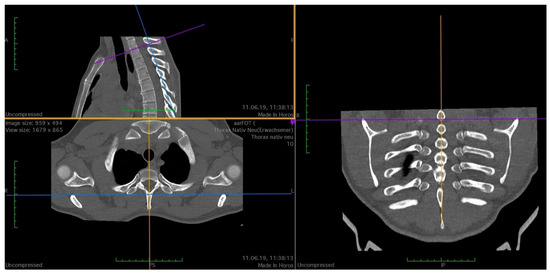

| Variable Name | Abbreviation | Description |

|---|---|---|

| Anterior to posterior rip extension | RAP | From the most ventral point of the caput costae 1, a perpendicular line to the tangent of the posterior edge of the first thoracic vertebral body. |

| Vertebral body width | VBW | Width of the first vertebral body at the level of the centre of the articulatio capitis costae 1 |

| Vertebral body depth | VBD | From anterior edge to posterior edge (most ventral point of vertebral foramen) of the first vertebral body |